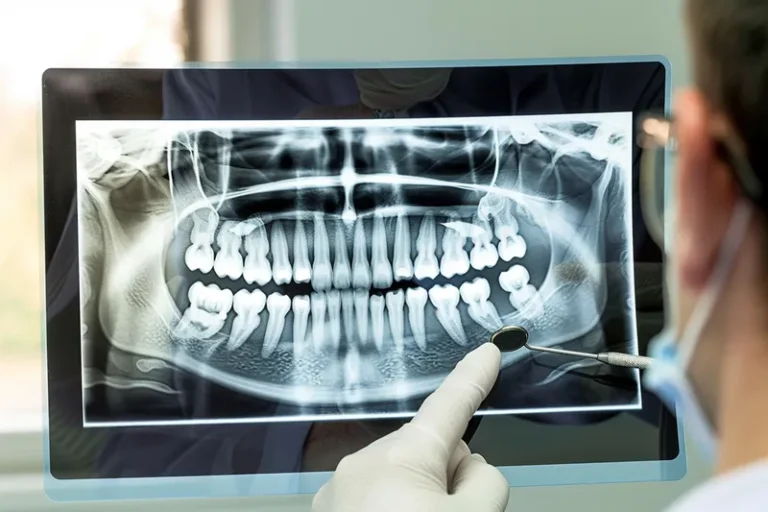

La osteointegración es el proceso biológico fundamental que determina el éxito de los implantes dentales. Durante este fenómeno, el hueso del maxilar crece y se fusiona directamente con la superficie del implante de titanio, creando una conexión estructural y funcional que garantiza la estabilidad a largo plazo. Este proceso, descubierto por el profesor Per-Ingvar Brånemark…

La sanación de un implante dental es un proceso gradual que varía según cada paciente. Generalmente, la integración completa del implante con el hueso (osteointegración) tarda entre 3 y 6 meses, aunque la recuperación inicial de los tejidos blandos ocurre en las primeras semanas. Durante este período, es fundamental seguir las indicaciones del especialista para…